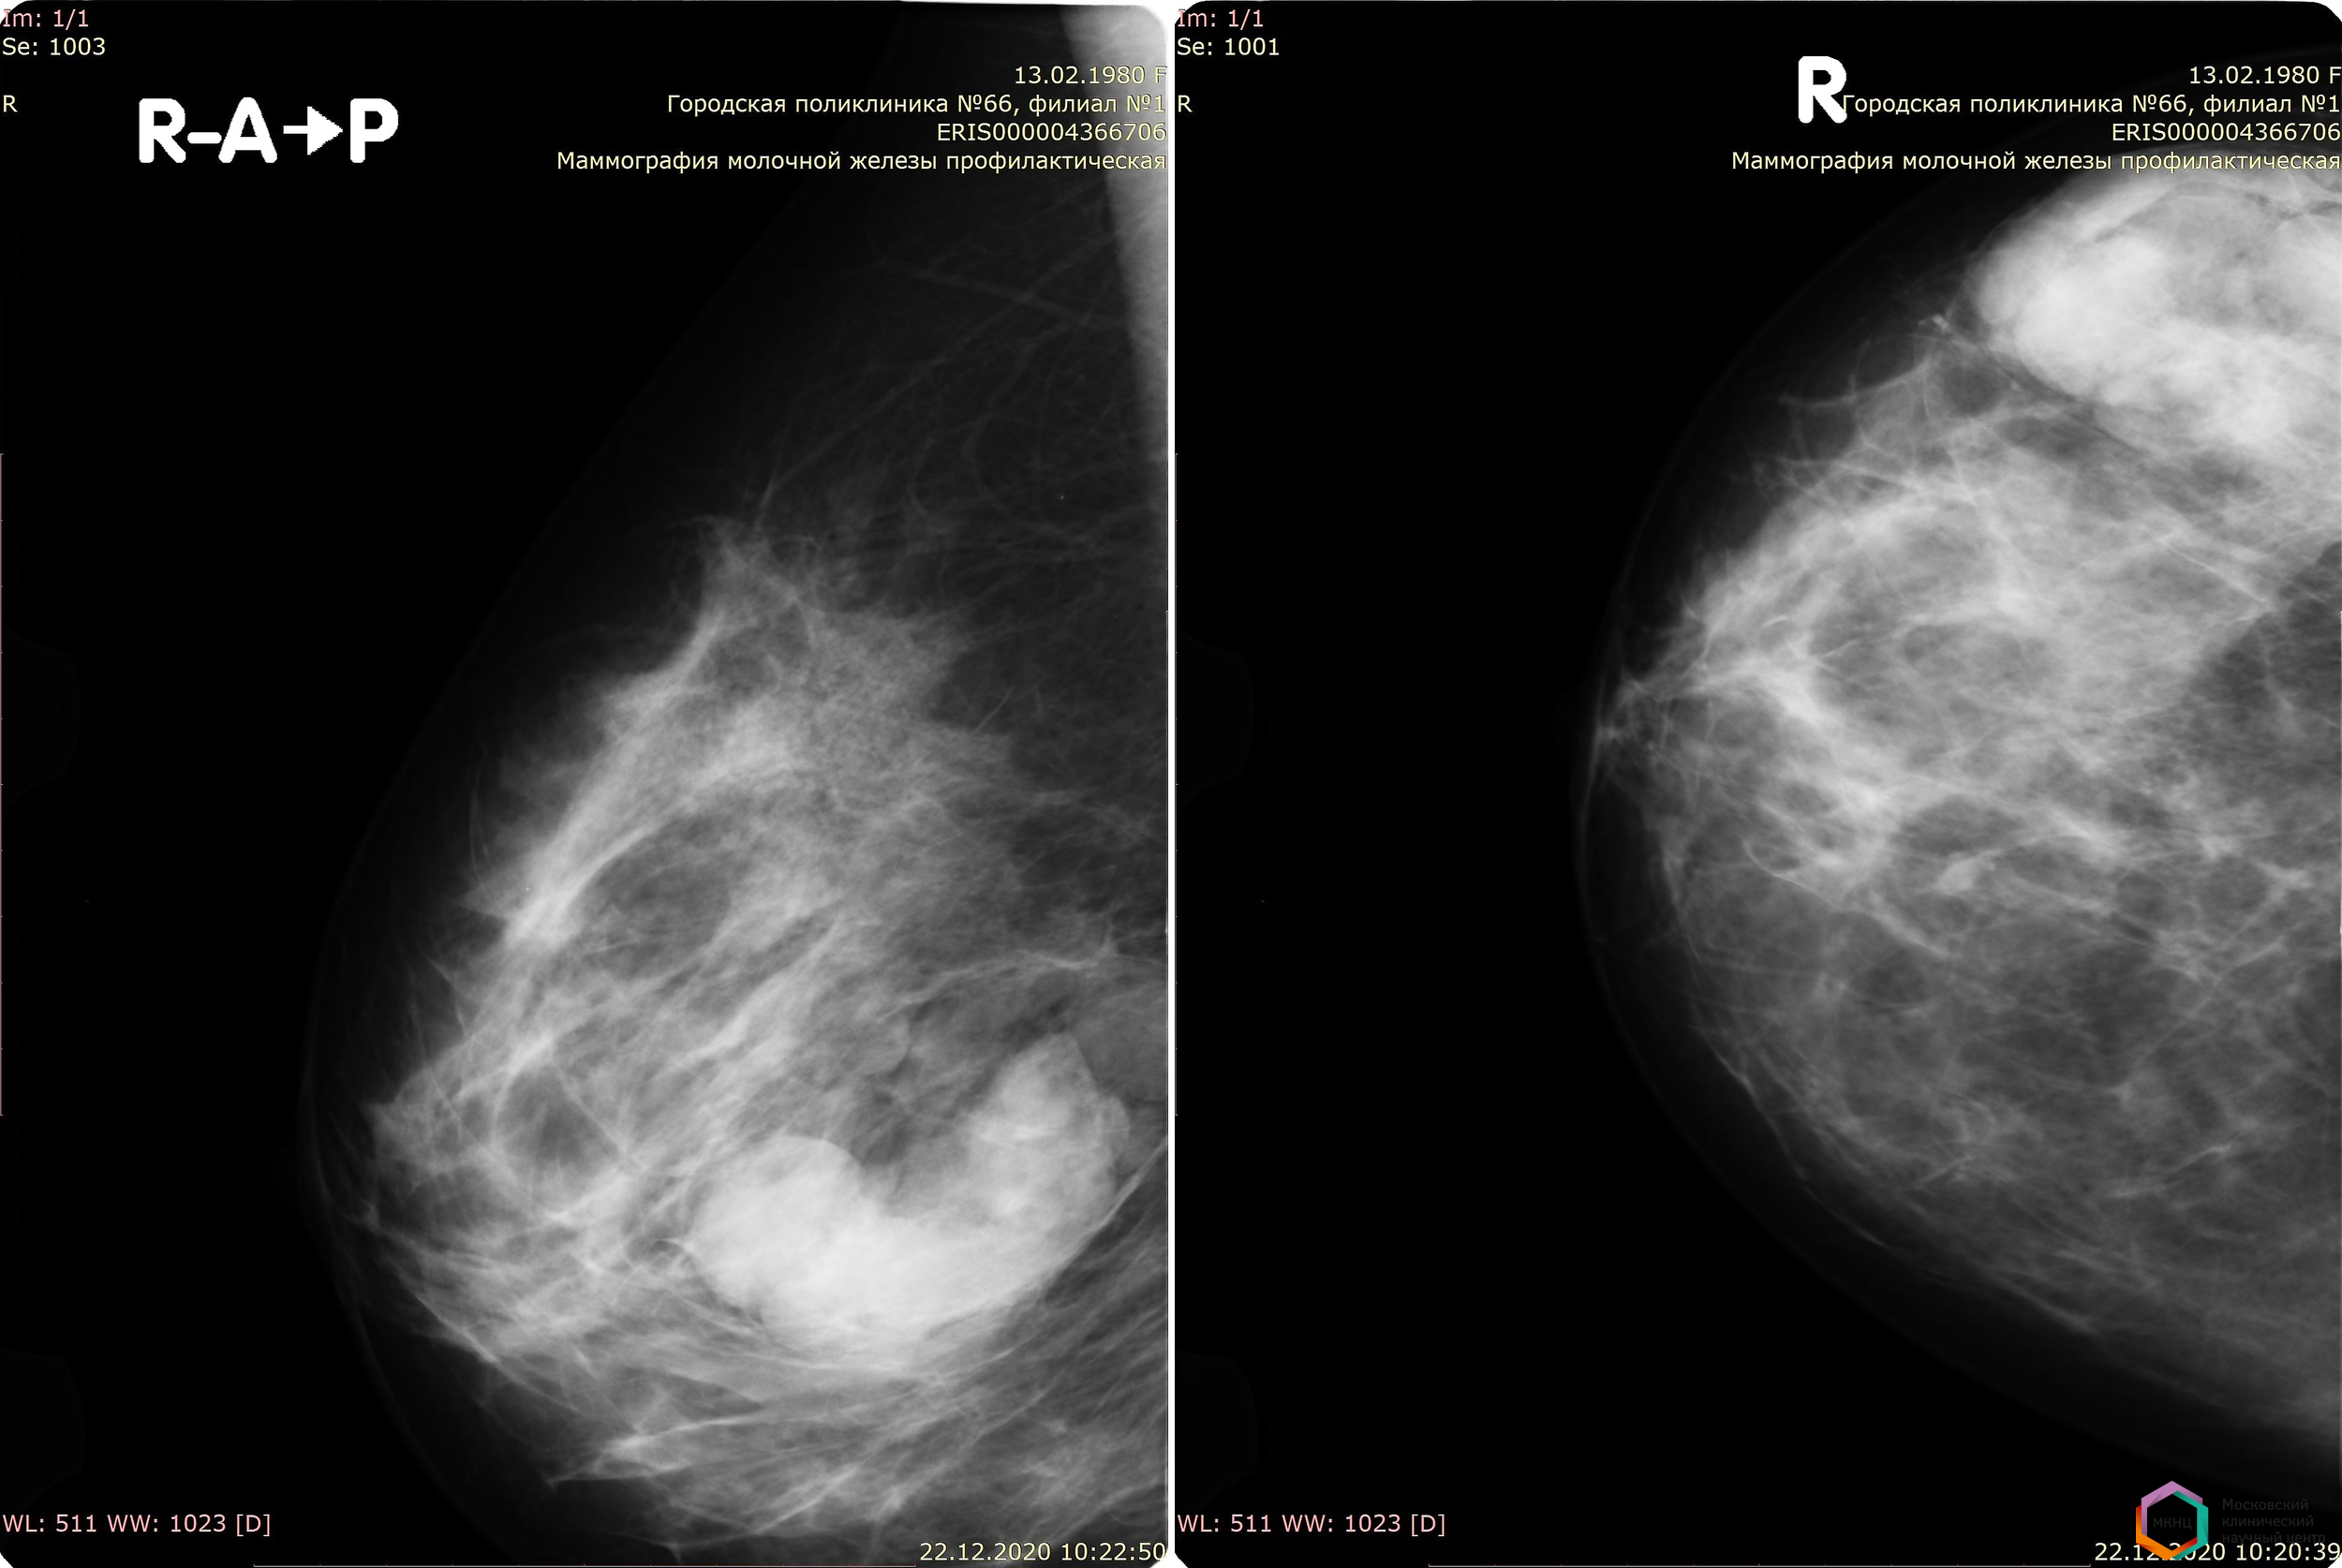

Фиброаденома молочной железы - доброкачественное образование, которое часто встречается у женщин. Оно может быть обнаружено при помощи различных методов диагностики, включая маммографию. Ниже представлены фотографии, помогающие понять, как выглядит данное заболевание.

Маммография и ее роль в диагностике фиброаденомы молочной железы

Маммография - это рентгенологическое исследование молочных желез. Оно позволяет выявить различные изменения в тканях, включая фиброаденому. На маммограммах можно увидеть структурные особенности опухоли и отследить ее динамику во времени.